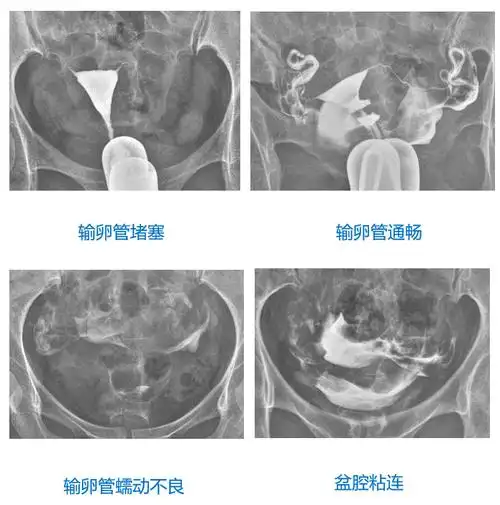

输卵管造影检查,只能判断输卵管的通畅度吗